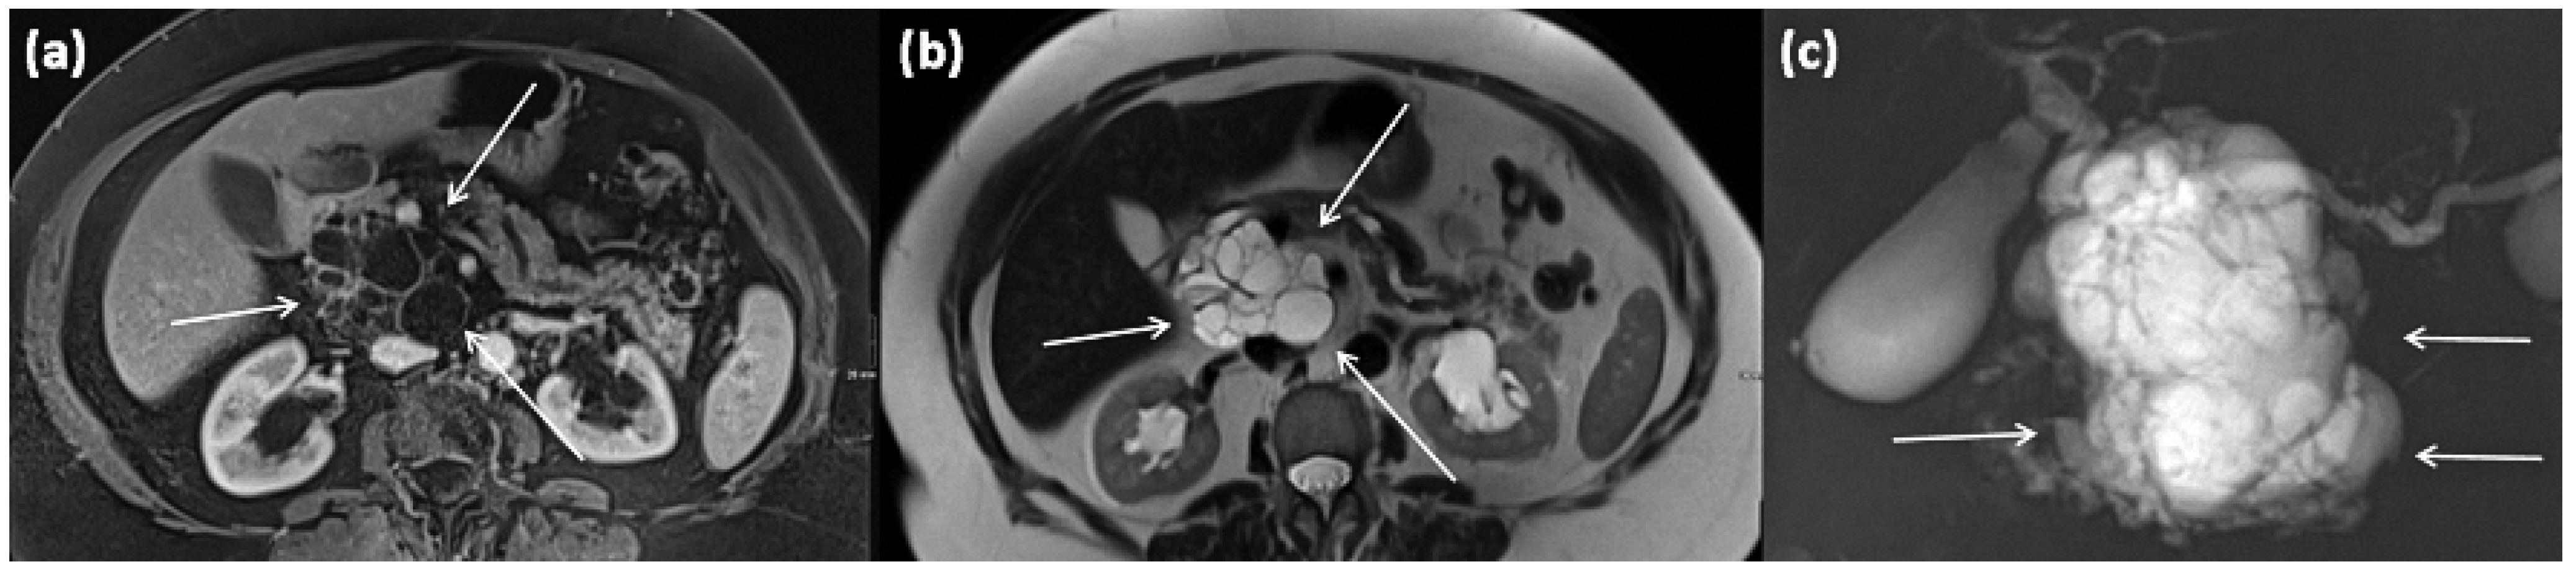

3.5.3. Mixed Type